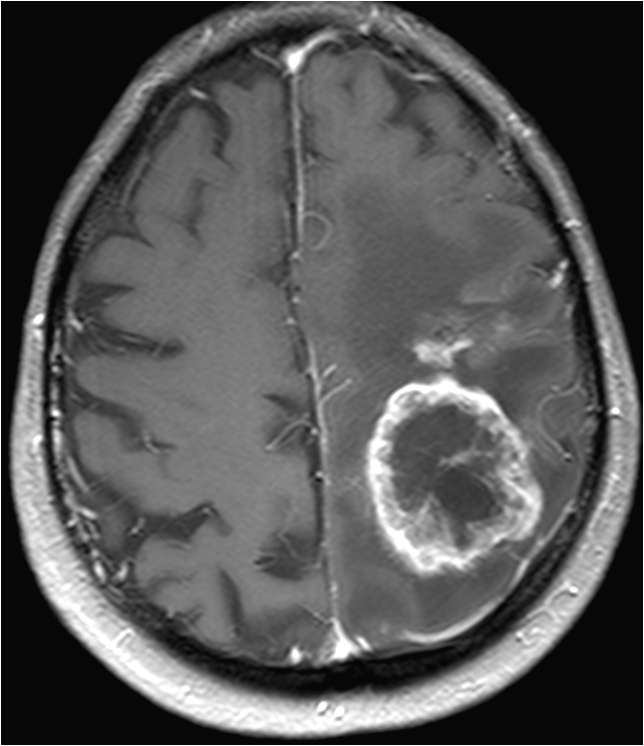

Patients with brain tumors may complain symptoms of headache, dizziness, vomiting, blurred vision, limbs weakness, etc.. Other symptoms include seizures and endocrine disorders; Personality or behavior changes may also occur. With modern advances in brain imaging technology, Computerized Tomography (CT) scan and magnetic resonance imaging (MRI) are the most commonly used diagnostic tools.

MRI does not involve radiation risk. Patients are required to lie inside the scanner with a strong magnetic field. Patients will not feel pain during the scanning process. MRI images can be achieved in a number of different angles and through a variety of different “signals”, so as to letting us to explore more about the tumors’ nature, thus allowing neurosurgeons making the most appropriate treatment plan for patients.